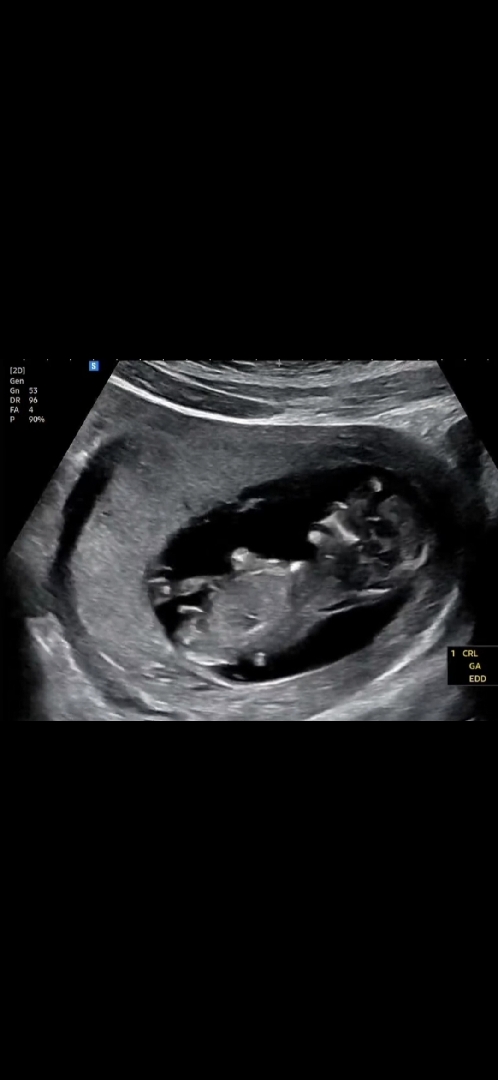

12주차 3일! 아들일까요 딸일까요

니프티를 안 해서 너무너무 궁금해요